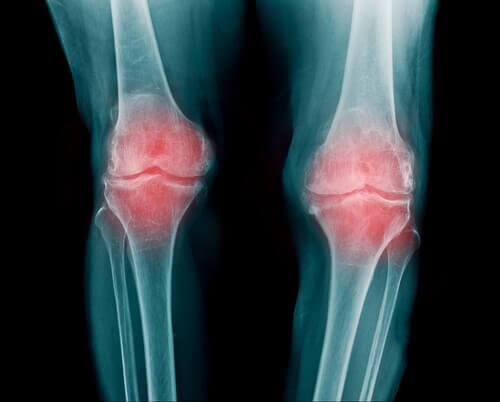

Reumatoïde artritis

- Reumatoïde artritis is een ontsteking van de gewrichten. Meerdere gewrichten kunnen worden aangedaan.

- Dat komt omdat er zich calciumafzettingen ophopen in het gewricht. De gewrichten gaan tintelen en het kraakbeen verzwakt, dat vervolgens geleidelijk afneemt en de pijn verergert.

- Over het algemeen zit de ziekte in de polsen, vingers en knieën. Deze ziekte wordt ook in verband gebracht met artrose en schildklieraandoeningen.